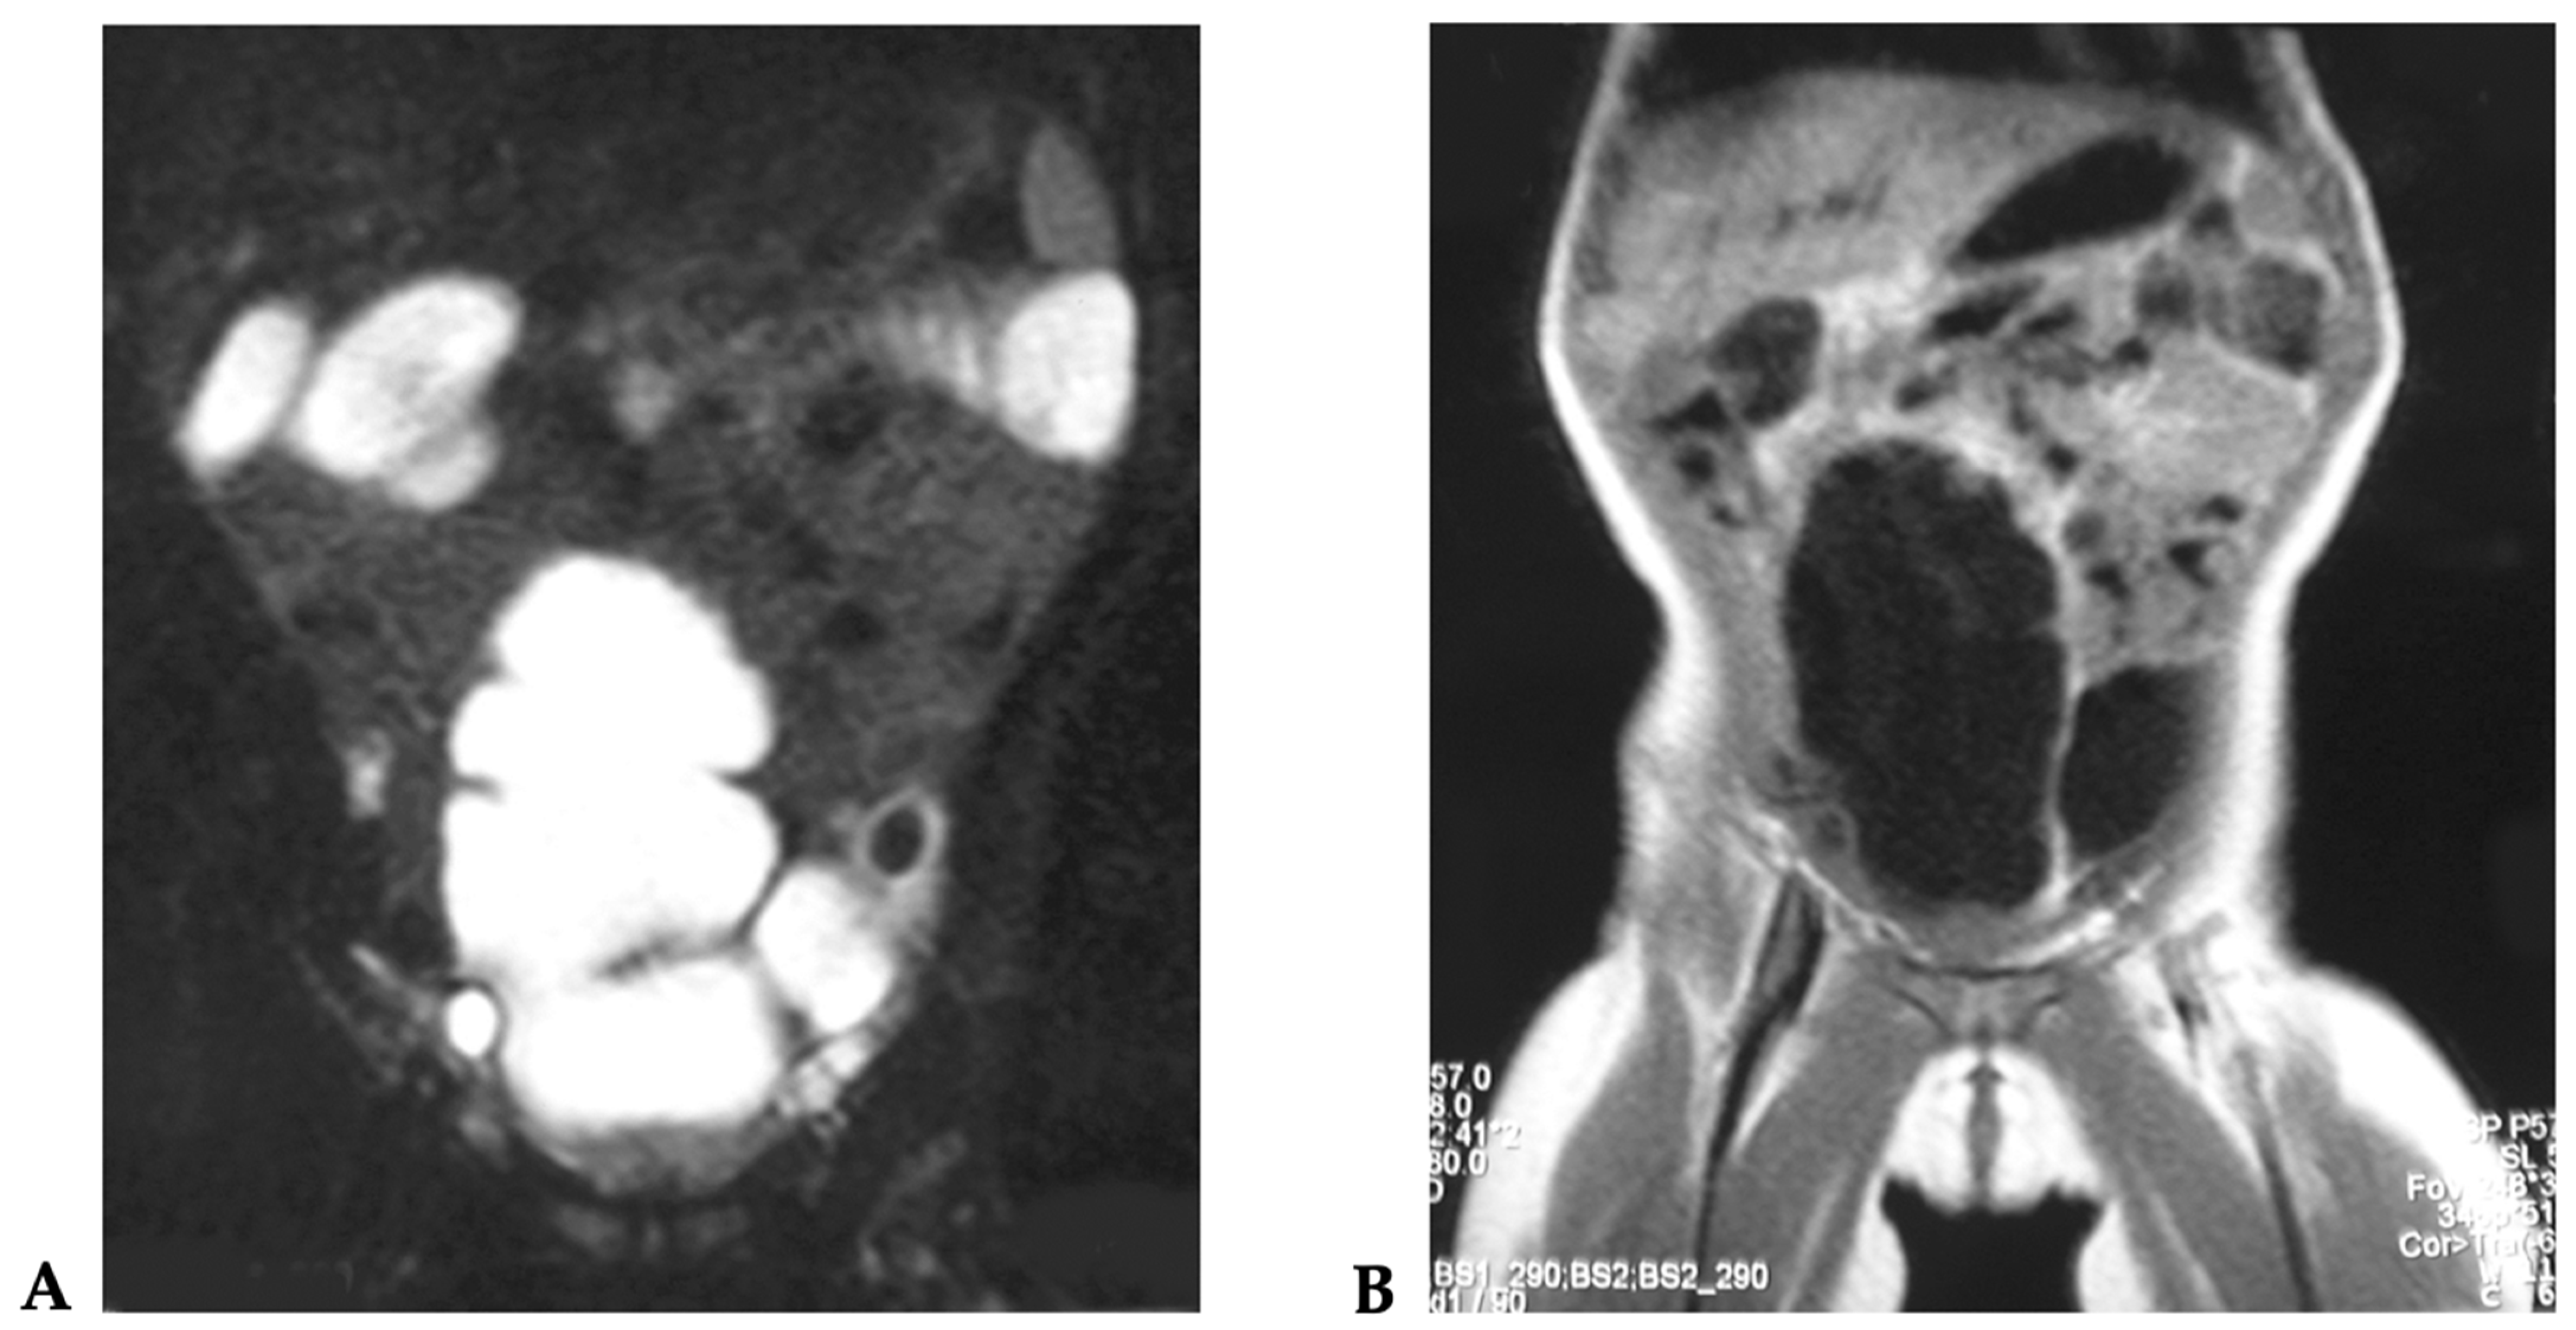

3.1. Case 1

3.2. Case 2